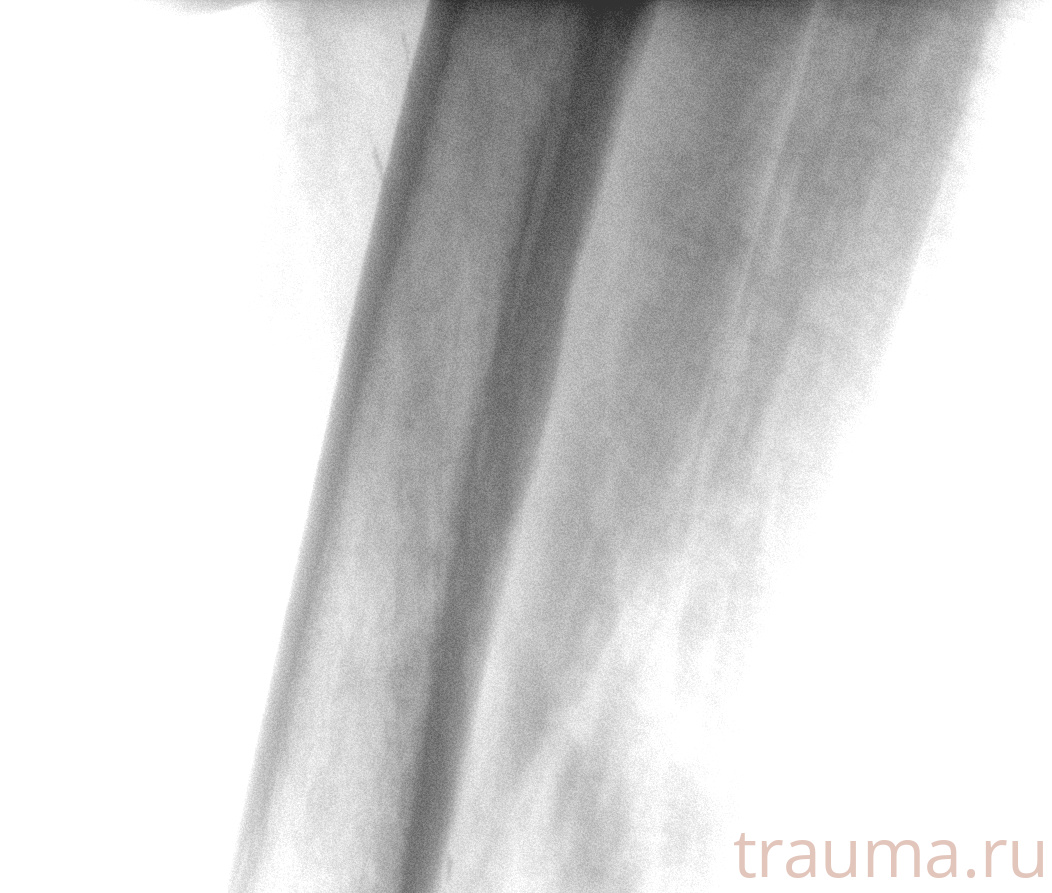

Рентгенограммы

Рентген на дому: по вашему адресу приезжает врач-рентгенолог, травматолог-ортопед с мобильным рентгеновским аппаратом, проводит диагностику травмы или заболевания, делает необходимые рентгенограммы, дает рекомендации по дальнейшему лечению. Получить качественные снимки в домашних условиях возможно благодаря уникальной методике, разработанной МосРентген Центром для института  Склифосовского